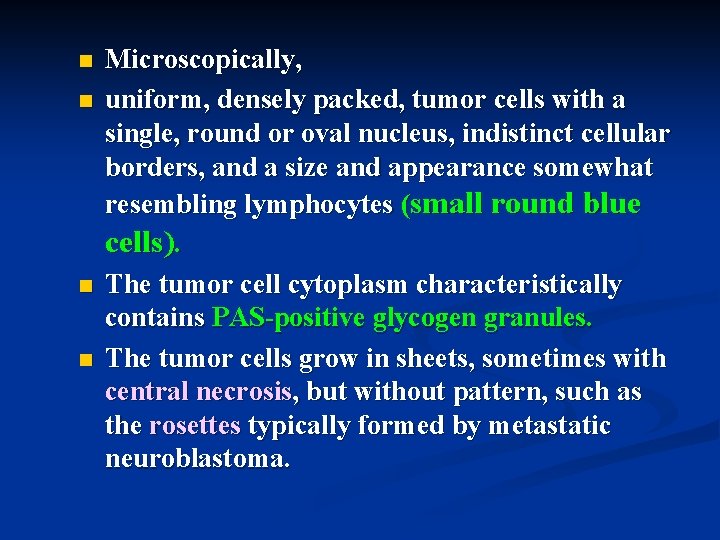

n n Microscopically, uniform, densely packed, tumor cells with a single, round or oval nucleus, indistinct cellular borders, and a size and appearance somewhat resembling lymphocytes (small round blue cells). The tumor cell cytoplasm characteristically contains PAS-positive glycogen granules. The tumor cells grow in sheets, sometimes with central necrosis, but without pattern, such as the rosettes typically formed by metastatic neuroblastoma.